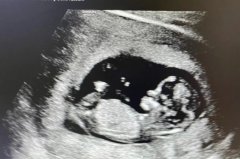

再说技术和实力。 为啥我常跟客人提到这家“首家”私立中心?因为它确实有资本。比如他们的胚胎实验室,用的是时差监控系统(Time-lapse),能24小时看着胚胎宝宝发育,挑那个最强壮的来移植。成功率的数据嘛,在他们官网是公开的,对于40岁以下的客人,一直挺亮眼的。但我得说句大实话:成功率是个参考,不是保证。 每个人的身体都是独一无二的田地。